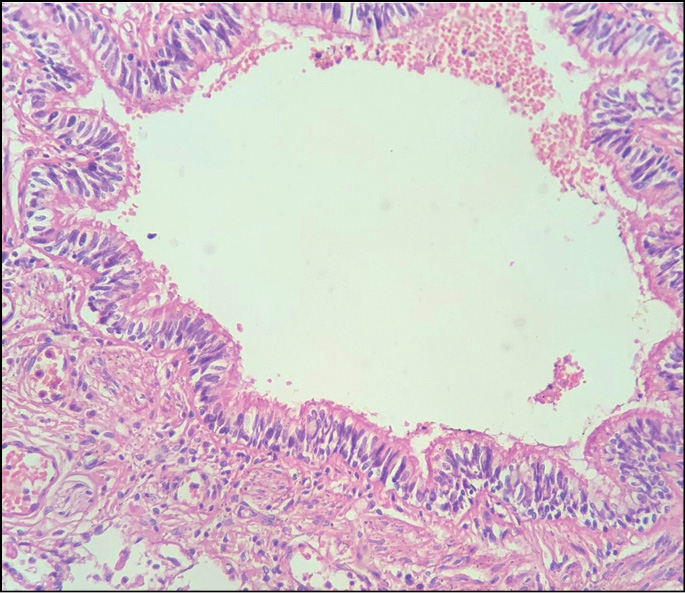

- очаги острой альвеолярной эмфиземы, дистелек-тазов, серозного отёка, интерстициального воспаления; мелкоочаговый альвеолит; нарушение гемодинамики в системе микроциркуляторного русла; в просветах сосудов эозинофилия разной степени выраженности (рис. 2); стенки бронхов с небольшой полиморфноклеточной инфильтрацией, наличием эозинофильных лейкоцитов (рис. 3); спазм бронхов и бронхиол (рис. 4), в просветах части бронхиол ― гомогенные бурые массы, клетки десквамированного эпителия (рис. 5); отёк висцеральной плевры;

Рис. 4. Спазм бронхиол. Окраска гематоксилином и эозином, ×20.